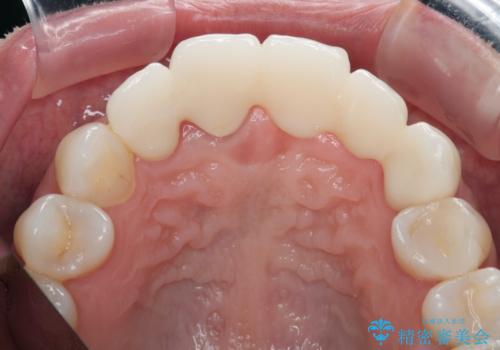

歯槽堤保存術を併用したブリッジ治療

- 前歯がグラグラし、においもする、とのことで改善を求めて来院されました。

一見して問題ないように見える左側の2前歯は、セラミックを除去してみると亀裂や虫歯の再発が見られました。

一件綺麗に見えるセラミックも適合や精度が悪いと、内部で虫歯が進行し亀裂や破折、悪臭の原因となることがあります。